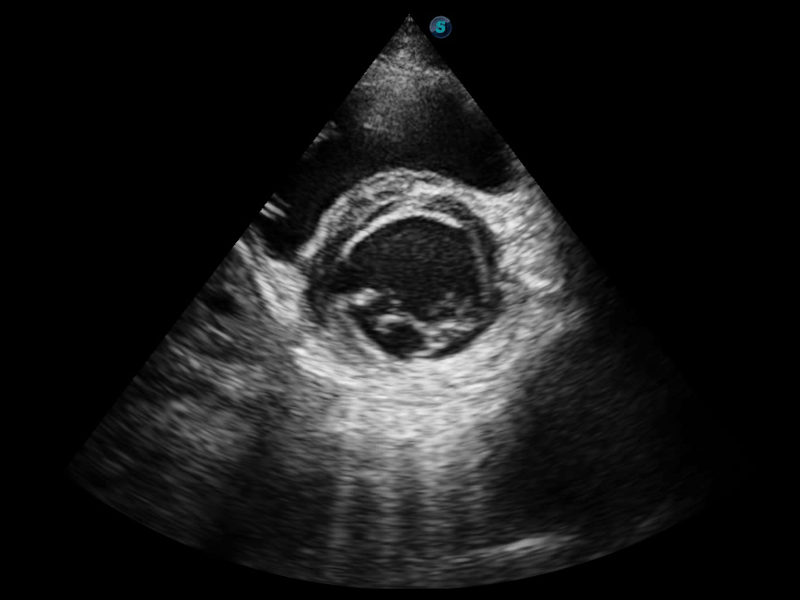

临床图像